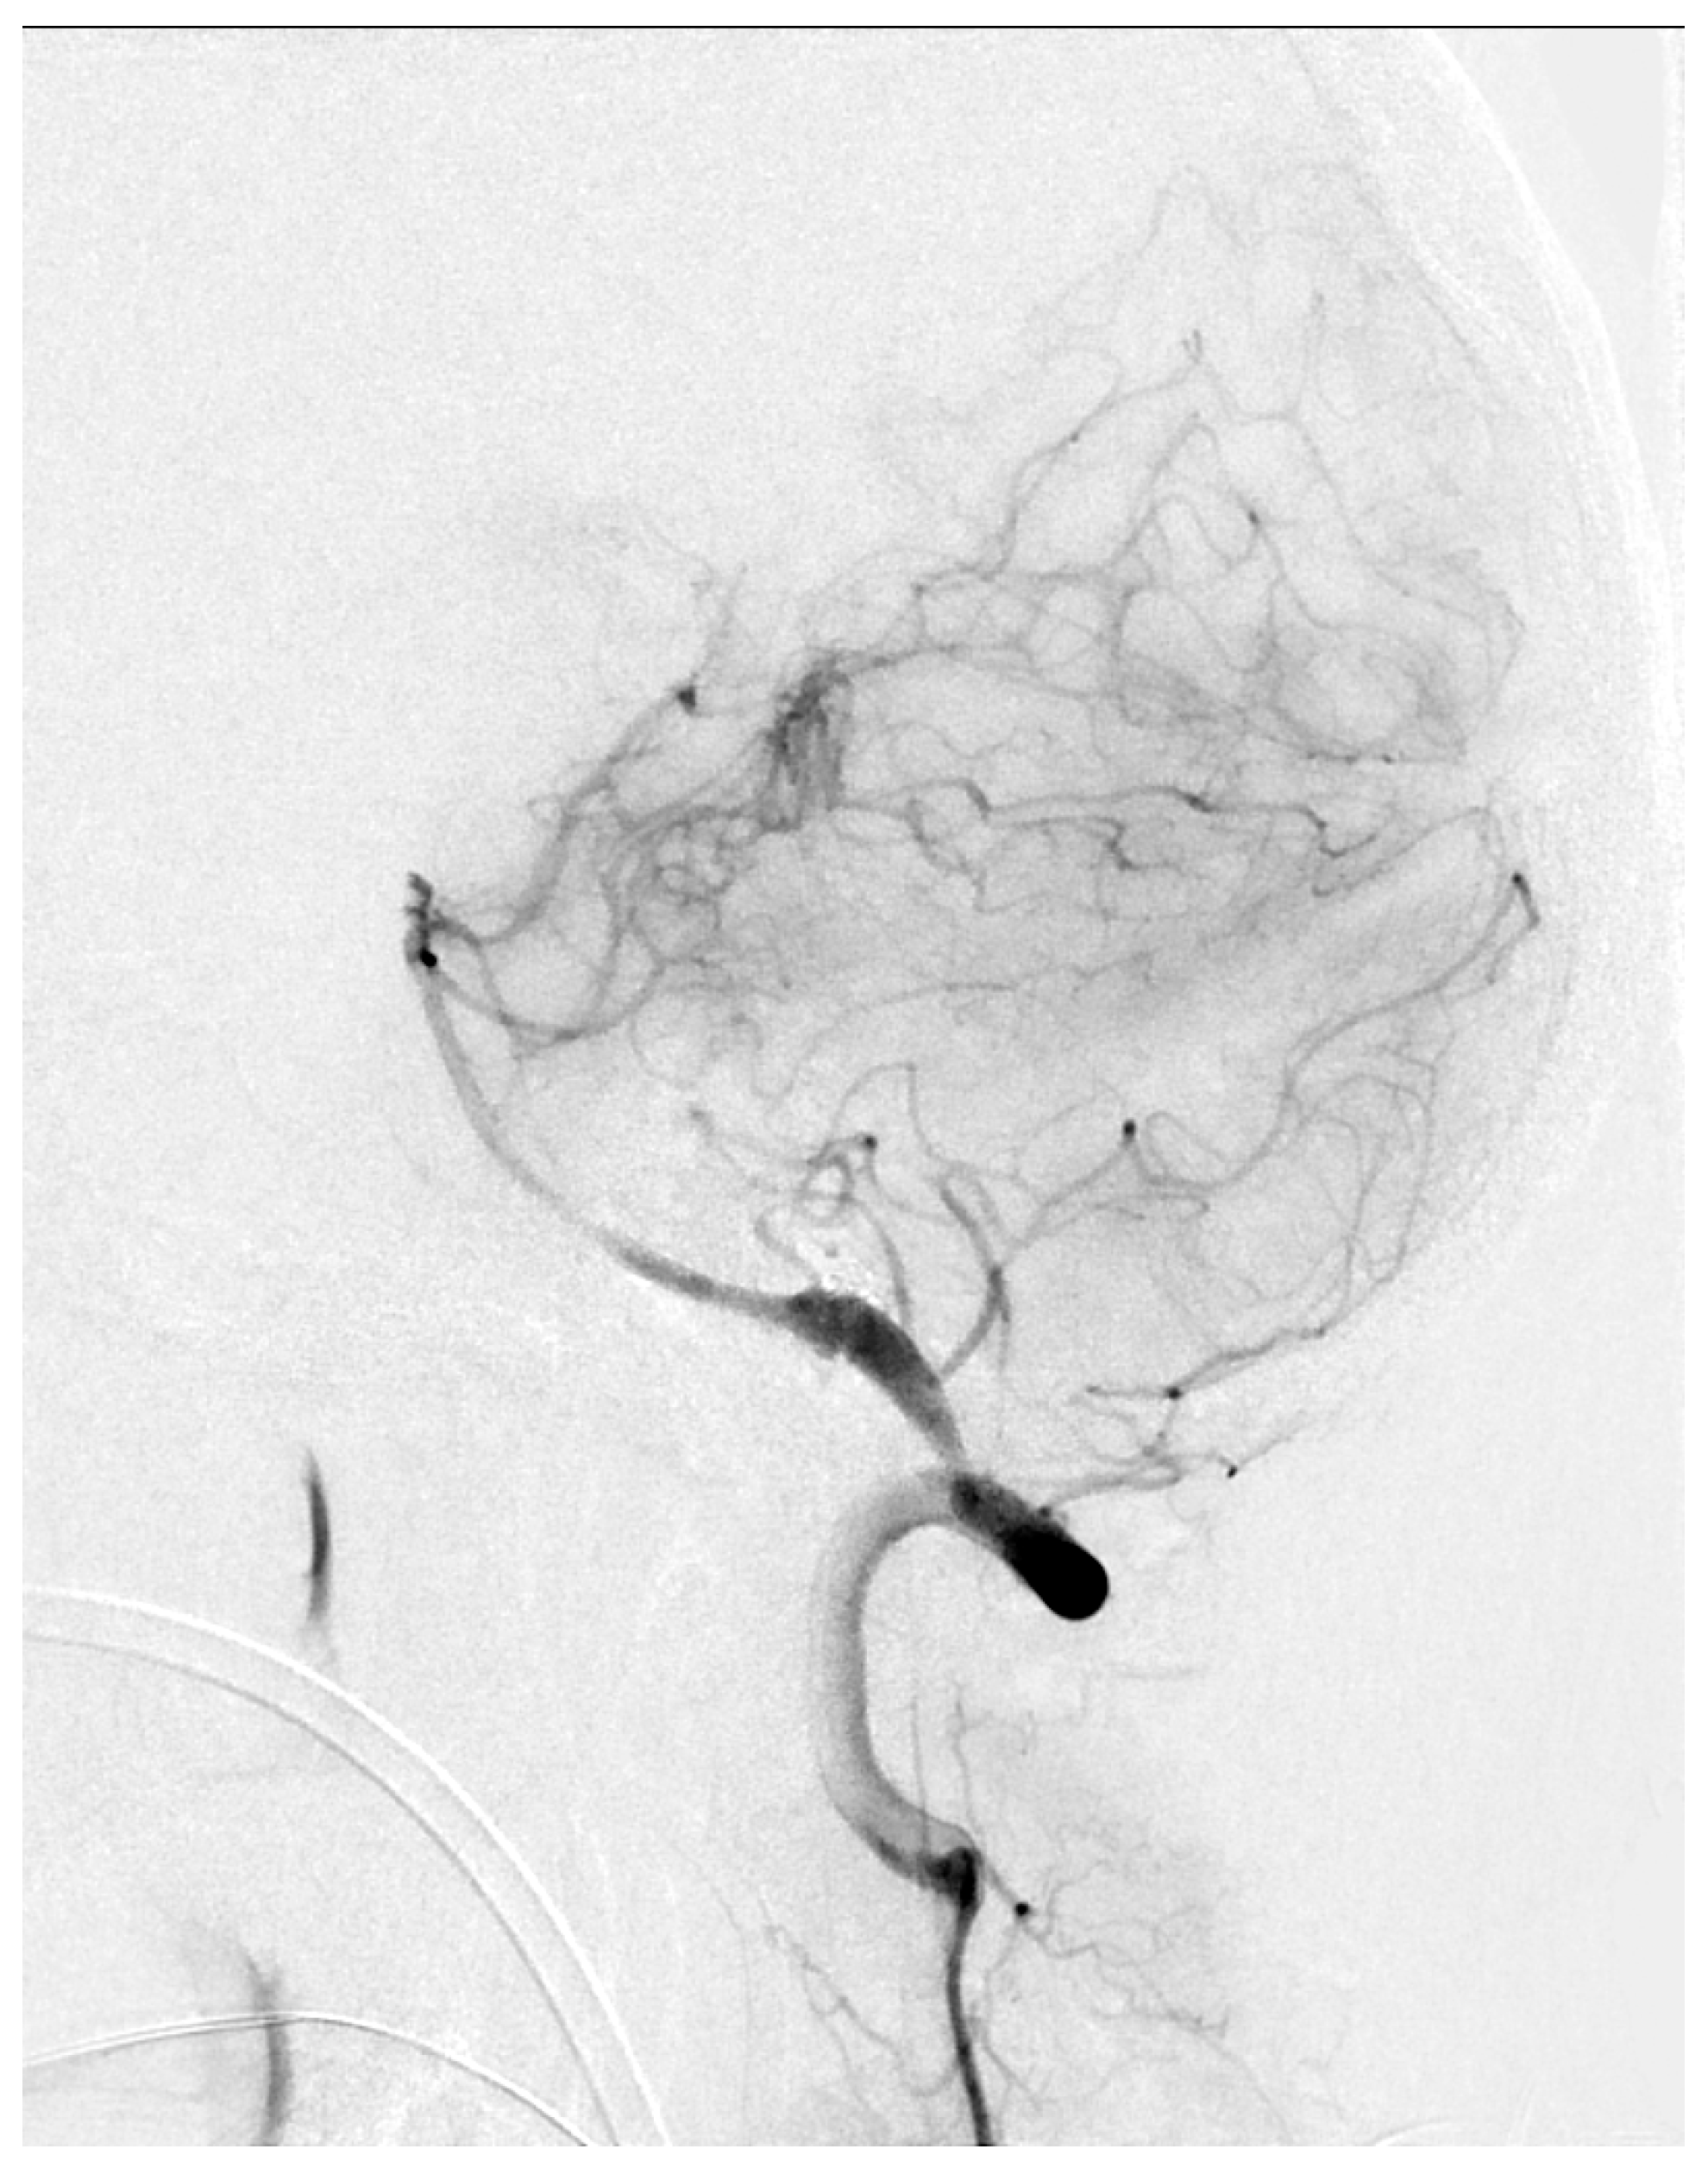

In our study, limb preconditioning prevented vasoconstriction in the mid-basilar artery, but for reasons which are not clear, no effects on the proximal or distal segments were seen. The mid-basilar segment may be more susceptible to vasoconstriction, given that the proximal and distal segments have arterial confluences (vertebrobasilar junction) or bifurcations (top of the basilar), which may confer a more stable vascular structure. We were not able to find clinical reports showing a susceptibility of the mid-basilar artery to vasospasm in human SAH. However, Figure 5 shows a catheter angiogram of a case of mid-basilar vasospasm in a patient with recent SAH, with sparing of the proximal and distal segments.

Figure 5.

Lateral view of basilar artery catheter angiogram in a patient with recent subarachnoid hemorrhage demonstrating mid-basilar artery vasospasm.